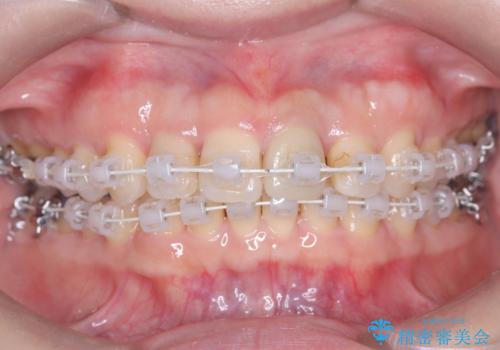

初期段階では、リンガルアーチを上顎に装着し、奥歯を少しずつ後方へ移動させていきました。これにより前歯部の歯列に十分なスペースを確保。その後、マルチブラケット(ワイヤー矯正)を用いて、突出した八重歯を正しい位置に誘導しながら、歯並び全体を整えていきました。